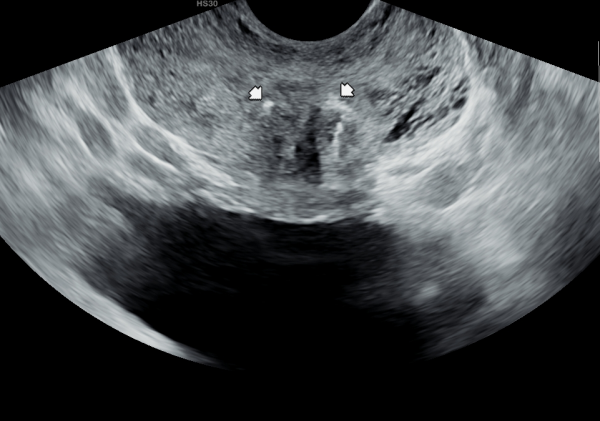

5년뒤 바쁜 일상 생활로 전립선의 관리를 하지 못하고 고환의 통증과 빈뇨 그리고 회음부 통증이 심해진다고 내원 당일 검사한 경직장 전립선 초음파 검사상 사정관 낭종과 낭종내 미세 결석이 생기고 사정관이 탈락된 상피 세포가 70%가량 좁아지고 전립선관도 순환 장애로 전립선 낭종이 관찰되는 초음파 사진입니다.

This transrectal prostate ultrasound image was taken on the day of the visit, five years later. Due to a busy lifestyle, the patient was unable to maintain prostate care and began experiencing worsening testicular pain, frequent urination, and perineal discomfort. The scan shows an ejaculatory duct cyst with microcalcifications inside, as well as narrowing of about 70% of the duct caused by accumulated epithelial cells. Circulatory issues have also led to the formation of prostatic cysts in the prostatic ducts.